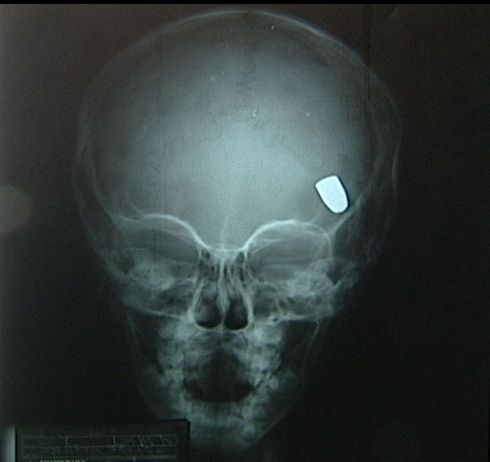

A tia de Samuel, Divalcir Oliveira, contou que a médica não quis dar pontos no ferimento, pois segundo ela, o procedimento deveria ter sido feito no primeiro dia. Como o menino não melhorou, a família pagou por um raio-x. A radiografia mostrou a bala dentro da cabeça de Samuel.

O neurocirugião que realizou a cirurgia em Samuel disse ter ficado impressionado com o raio-x. A operação foi feita com tranquilidade. Samuel já saiu da UTI e, segundo o médico, não deve ter sequelas.